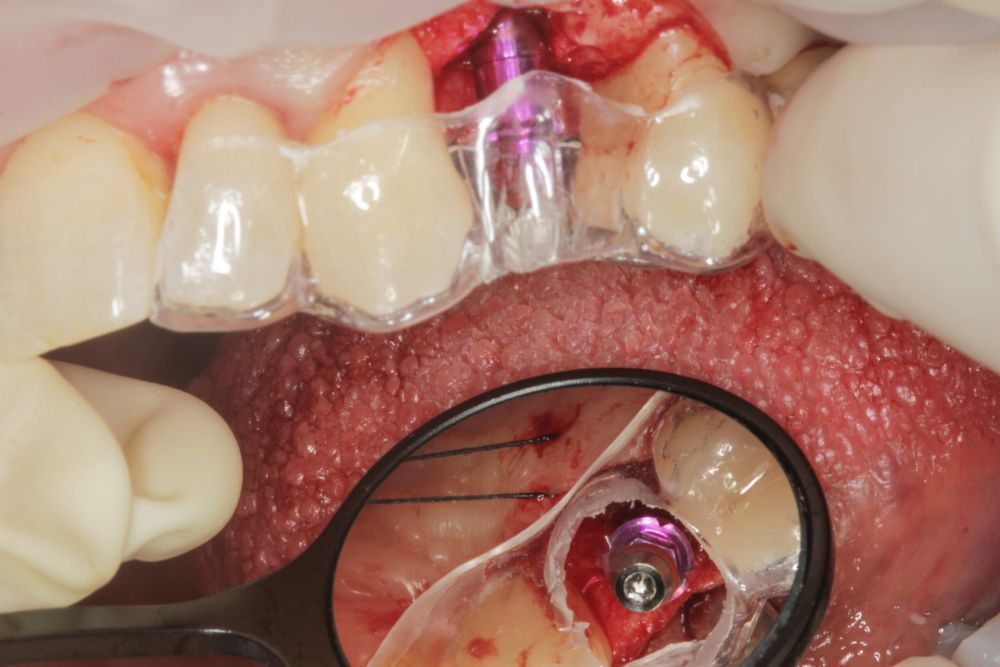

En cuanto a la rehabilitación protésica, en todos los casos se utilizó una prótesis atornillada con transepitelial para prótesis unitaria. La supervivencia de las prótesis fue del 100%, sin encontrarse fracaso en ninguna de ellas al igual que los implantes, con un tiempo de seguimiento de tres años. Durante el primer año, en las visitas de control, ninguno de los implantes mostró sangrado al sondaje ni inflamación de los tejidos periimplantarios. La media de la pérdida ósea en este punto fue de 0,32 mm (+/- 0,60) y la media de la pérdida ósea distal de 0,31 (+/- 0,48). A los dos años, no se registraron tampoco signos inflamatorios en ninguno de los implantes y la pérdida ósea mesial del conjunto fue de media de 0,38 mm (+- 0,54) y la distal de 0,64 mm (+/- 0,70). En la última visita a los 3 años, los tejidos periimplantarios siguieron estables, sin signos de inflamación y la media de la pérdida ósea mesial fue de 0,40 mm (+/- 0,53) y la distal de 0,69 (+/- 0,55) (Figura 5). En las Figuras 6-12 se muestra uno de los casos incluidos en el estudio.